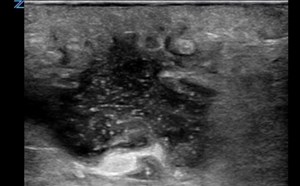

Abscess Evaluation